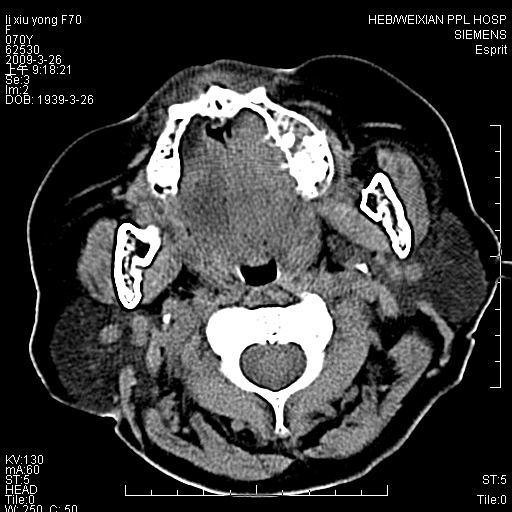

老年患者,女。鼻塞多年。

考虑右侧上颌窦良性占位性病变,粘液囊肿可能性大;建议活检。

膨胀性生长,且骨质无破坏,说明时间久,良性;从密度,边缘看,内部还见坏死区,应该是实性肿瘤,定性,影像学无绝对的特异性

病灶密度很不均匀,骨壁膨胀中有断裂,考虑内翻乳头状瘤可能性大,粘液囊肿不排除

膨胀性生长,且骨质无破坏,说明时间久,良性;从密度,边缘看,内部还见坏死区,应该是实性肿瘤,定性,影像学无绝对的特异性,考虑内翻性乳头状瘤可能